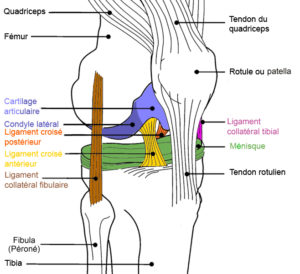

A quoi servent les ligaments croisés ? Il existe deux ligaments croisés dans le genou : un antérieur (LCA) et le second postérieur (LCP). Ces deux ligaments se croisent d’avant en arrière et latéralement entre le fémur et le tibia. Leur rôle est de maintenir une bonne stabilité du genou notamment dans